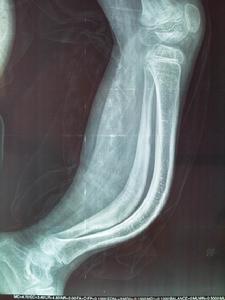

X線表現檢查。

成骨不全骨質疏鬆和骨的脆性增加。